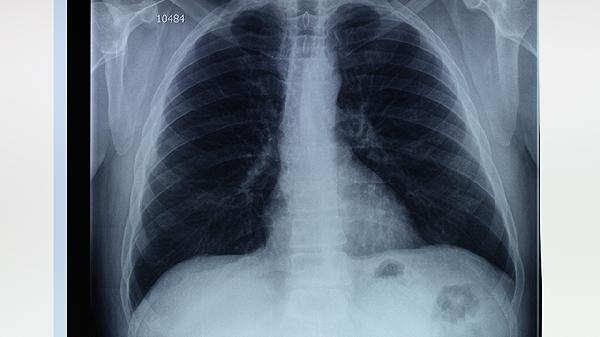

肺大泡是肺癌早期吗

肺大泡不是肺癌的早期表现,但两者可能存在一定关联,需通过影像学检查明确诊断并采取相应治疗。肺大泡是肺泡壁破裂后形成的含气囊腔,通常由慢性阻塞性肺疾病、肺气肿或肺部感染引起;肺癌则是肺部细胞的恶性增殖,早期症状不明显,晚期可能出现咳嗽、胸痛等症状。

肺大泡本身并非癌前病变,但部分肺癌可能发生在肺大泡周围或内部,影像学上表现为囊腔壁增厚或结节样改变。肺大泡患者因肺部结构异常,可能增加肺癌的易感性,尤其是长期吸烟者。临床中需结合病史、影像学及病理检查综合判断。